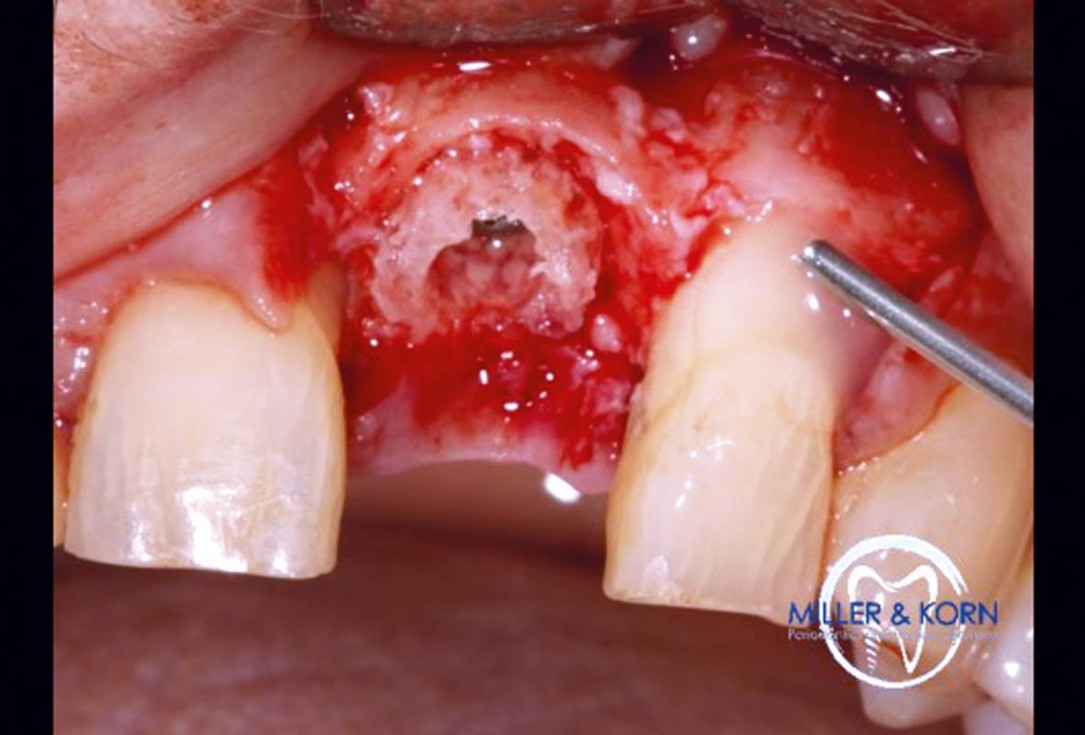

24/39 - Application of cerabone®Immediate implant placement and correction of horizontal and vertical bone loss using an allograft bone ring, cerabone® and Jason® membrane - Drs. Miller and Korn

-